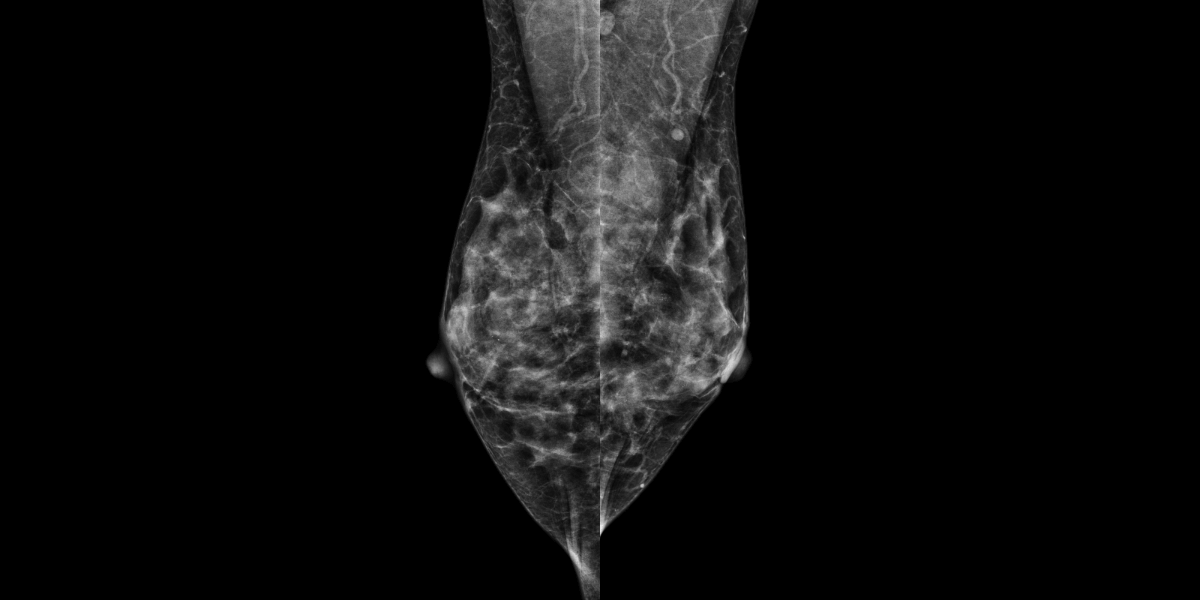

A 42 year-old female comes for palpable nodules of the left breast. MammoScreen® points to suspicious lesions of the left breast. The ultrasound reveals several nodular formations on both breasts. A breast MRI complement shows two left breast masses. Biopsy confirms invasive carcinoma SBR I, RH+, HER2-.